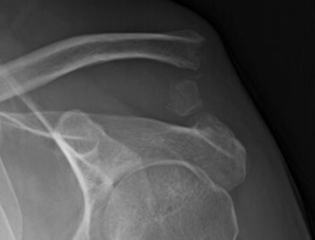

Grade 5 AC separation equivalent with distal clavicle fracture

Tensioned cerclage repair of AC joint with bone tunnels

A shoulder separation, also known as an AC separation, is diagnosed clinically with a large prominence seen at the AC joint. An xray is performed which shows the clavicle superior to the acromion process of the scapula.